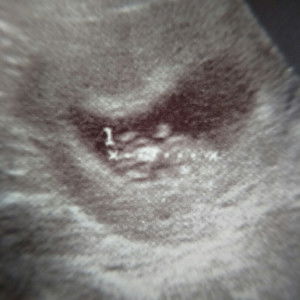

8w คะ เอเลี่ยนน้อย

8weeks ค่ะ